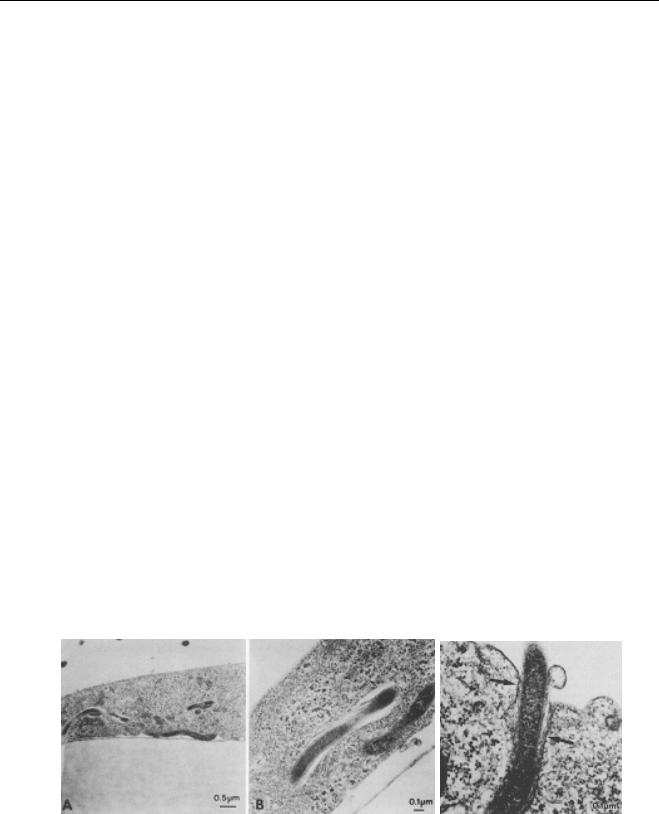

Tris-HCl (10mM), 3µl MgCl2 (1.5 mM), 8µl dNTP mix (1,25mM), 0.25µl

TaqDNA polimerase (1.5U) e 29,25µl de H

2

O Milli Q. Adicionou-se 1,5µl de

DMSO por amostra (concentração final 3%).

flgE 470 FW (5’- CGCCTATTCTAACTTGACCTGAAT – 3’)

flgE 470 Rev (5’- CAACTCTAAGCTCAAGAACACCAA – 3’)

Para este primer, os ciclos de temperatura e tempo para a reação

consistiram em uma desnaturação inicial por 3 minutos a 95ºC, seguida de

um de 35 ciclos, cada um consistindo em uma desnaturação a 95ºC por 45

segundos, anelamento a 64ºC por 45 segundos e extensão a 72ºC por 45

segundos.